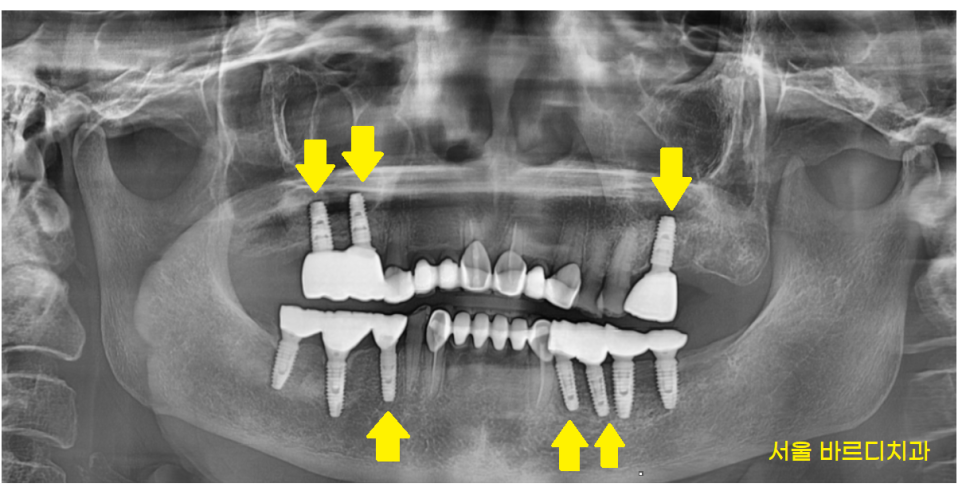

임플란트 이곳 저곳 해야해요

23.06.13

식사를 할 수 있는

어금니가 여러군데 빠진채로 내원해주신 환자분입니다.

치아 개수가 빠진게 많다보니

그러려니~ 하고

사셨다고 하네요ㅠㅠ

오른쪽 왼쪽 각각 1개 치아만

물리고 있는 상황이라

더이상은 버티시기 힘드셨대요

임플란트 위아래 합하여 6개

식립이 필요하다

명일동 치과에서 상담을 진행해드렸습니다.

23.07.25

윗니 어금니의 경우

코 막을 들어올리는 상악동 거상술이 필요했기 때문입니다.